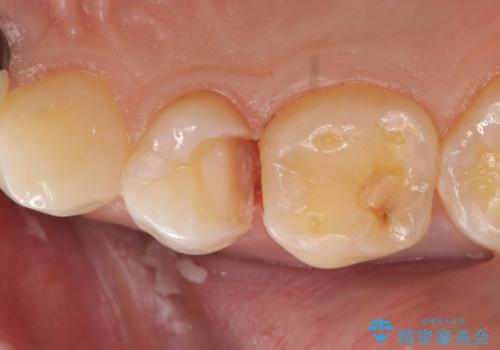

- 「歯がたまに痛む」を主訴に来院された患者様です。 見た目では齲窩が無いように見えますが、レントゲンを撮ると神経の近くまで達する深い虫歯だとわかりました。

虫歯を除去後セラミックインレーで治療を行いました。隣の子どもの歯のEも虫歯になっていたので同時に治療を行いました。

神経の近くまで虫歯が広がっていましたが、神経を保存して治療を行うことが出来ました。

見た目も凄く綺麗になり痛みも無く経過も良好なので、患者様も大変ご満足されていました。